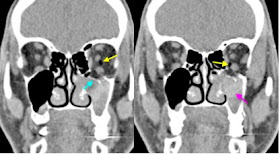

Axial Janela de CAI. Note no lado esquerdo normal (Seta longa) a intima relação da cabeça do martelo com o corpo da bigorna, transformando o espaço articular em uma epécie de cavidade virtual. Já no lado direito, observa-se um "gap" entre essas duas estruturas osseas (Seta curta). Coexiste preenchimento da orelha média direito por material isodenso.

Axial Janela de CAI (Plano superior à primeira foto). Note a marcada perda de contato entre a cabeça do martelo e corpo da bigorna (Seta longa), que configura um "gap" de aproximadamente 1,3 mm. Compare com o lado normal (Seta curta).

Sagital Janela de CAI. Comparando o lado normal (Circulo contínuo) com o lado alterado (Circulo pontilhado), fica evidente a perda de contanto do martelo com a bigorna. Luxação pós-traumática da articulação incudomaleolar.

Axial Janela de CAI. As setas revelam a presença de fratura na parede anterior do conduto auditivo externo do lado direito, que se estende sutilmente até a asa menor do esfenoide, onde se observa pequeno fragmento ósseo.